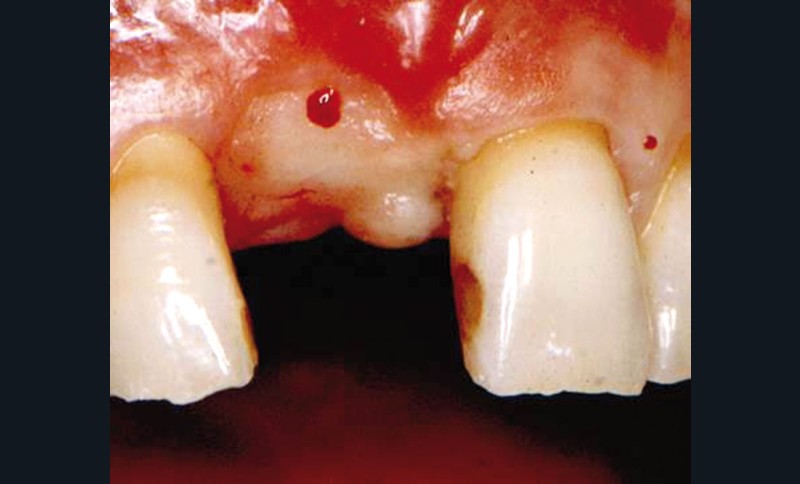

Le volume osseux résiduel était suffisant pour placer un implant en bonne position sans utiliser des techniques de régénération et, au bout de 6 mois, le deuxième temps chirurgical a été planifié. À ce moment-là, l’observation clinique montre une zone crestale plate entre les deux dents adjacentes avec un PIS de 0 (fig. 1, 2).